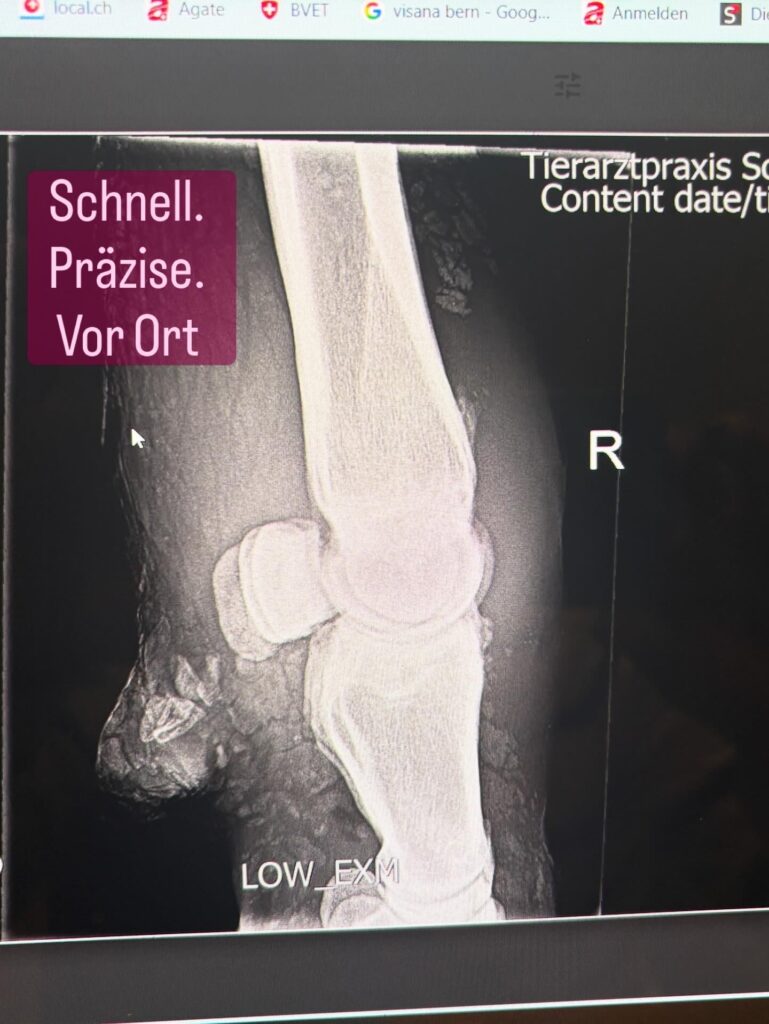

Eine Kuh, die trotz Behandlung nur langsam Fortschritte machte, erforderte eine genauere Abklärung. Mit unserem mobilen Röntgengerät für Nutztiere konnten wir die Situation direkt im Stall beurteilen – ohne zusätzlichen Transport und ohne zusätzlichen Stress für das Tier.

Gerade in solchen Momenten ist es entscheidend, möglichst rasch Klarheit zu gewinnen:

Besteht eine knöcherne Beteiligung? Wie ist die Prognose einzuschätzen? Und welche nächsten Schritte sind sinnvoll?

Die Möglichkeit, diese Fragen unmittelbar vor Ort zu klären, ist eine grosse Erleichterung – für die Kuh und für den Tierhalter.

Mobiles Röntgen bei Kühen im Stall gehört zu den Leistungen, die aktuell in unserer Region praktisch nicht angeboten werden.